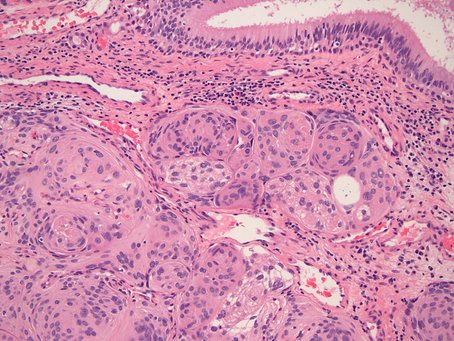

GYN Case 2. Hysterectomy from a young patient in 20s

•Diagnosis: epithelioid trophoblastic tumor